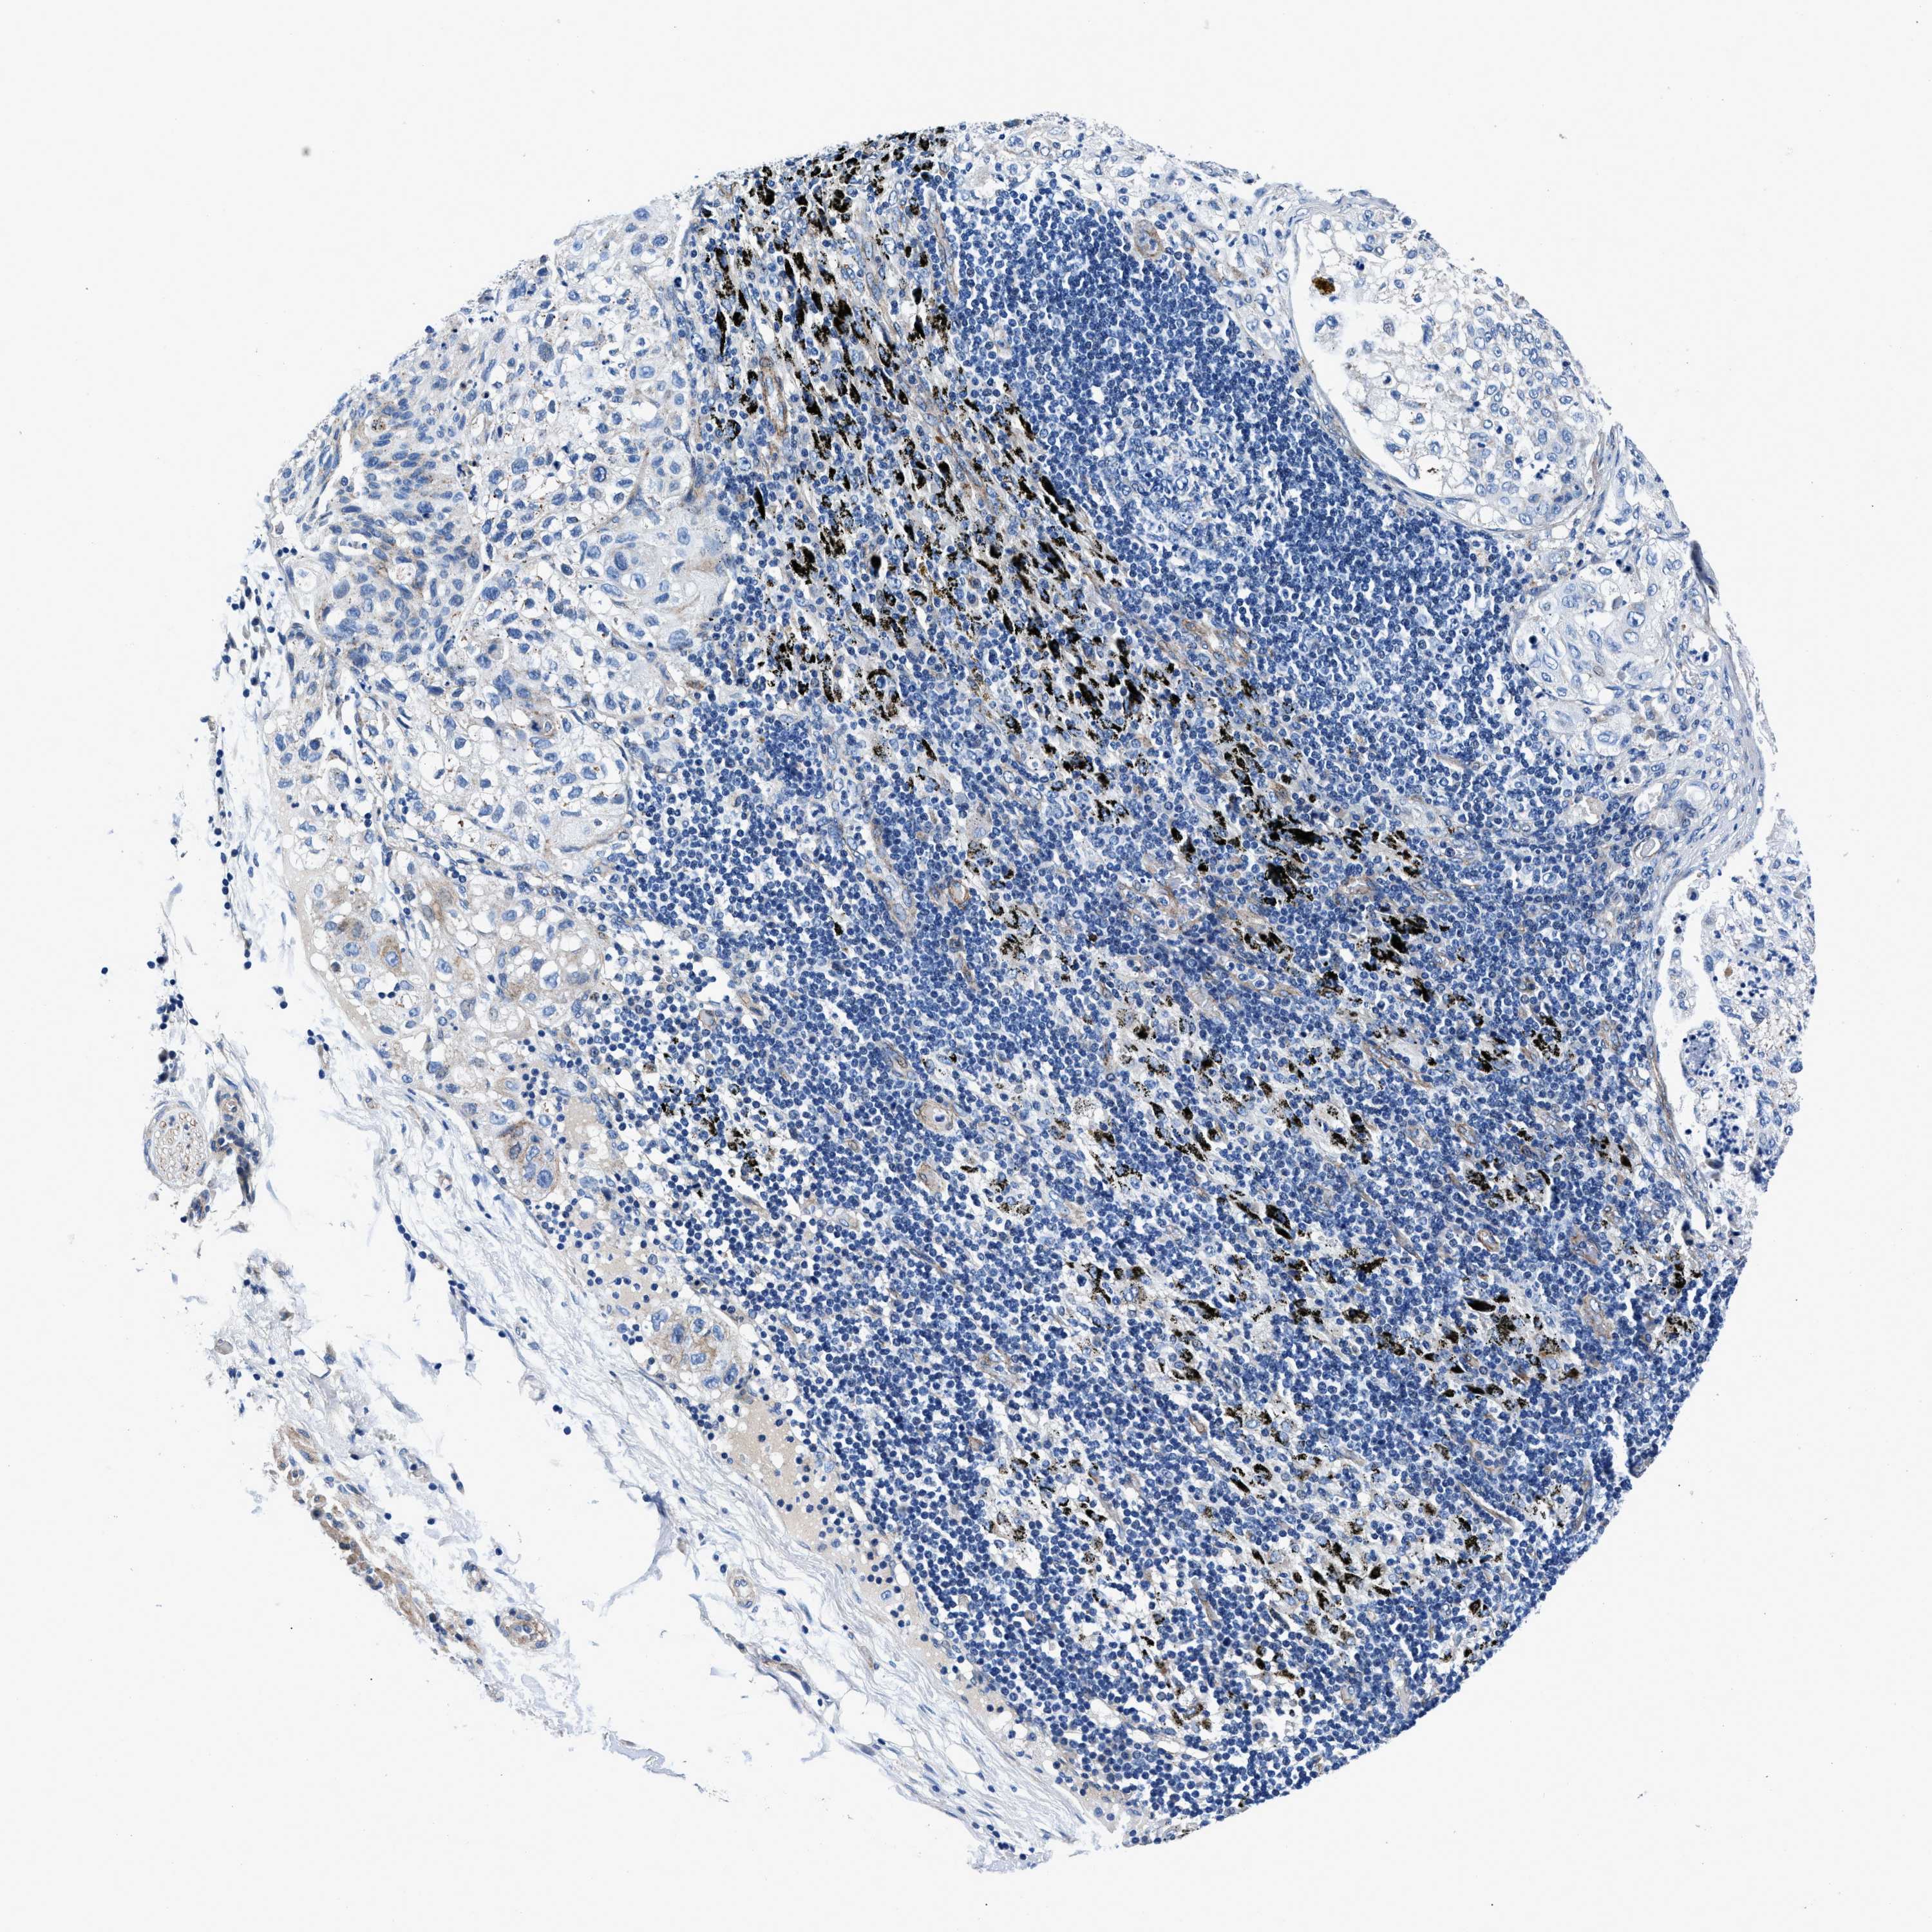

LUNG SQUAMOUS CELL CARCINOMA (TCGA) - Interactive survival scatter ploti

The Survival Scatter plot shows the clinical status (i.e. dead or alive) for all individuals in the patient cohort, based on the same data that underlies the corresponding Kaplan-Meier plots. Patients that are alive at last time for follow-up are shown in blue and patients who have died during the study are shown in red.

The x-axis shows the expression levels (FPKM) of the investigated gene in the tumor tissue at the time of diagnosis. The y-axis shows the follow-up time after diagnosis (years). Both axes are complimented with kernel density curves demonstrating the data density over the axes. The top density plot shows the expression levels (FPKM) distribution among dead (red) and alive patients (blue). The right density plot shows the data density of the survived years of dead patients with high and low expression levels respectively, stratified using the cutoff indicated by the vertical dashed line through the Survival Scatter plot. This cutoff is automatically defined based on the FPKM cutoff that minimizes the p-score. The cutoff can be changed by dragging the vertical line or by entering a cutoff value in the square labeled "Current cut-off".

Under the Survival Scatter plot the p-score landscape (black curve; left axis) is shown together with dead median separation (red curve; right axis). Dead median separation is the difference in median mRNA expression between patients who have died with high and low expression, respectively. It is calculated as follows: median FPKM expression of dead patients with high expression - median FPKM expression of dead patients with low expression. This is intended to aid the user in visually exploring custom cutoffs and the associated p-scores and dead median separation.

Individual patient data is displayed and can be filtered by clicking on one or more of the category buttons on the top of the page. Categories describing expression level and patient information include: high, low, alive, dead, female, male and tumor stages. The scale of the x-axis can be toggled between linear and log-scale by clicking on the "x log" button. Mouse-over function shows TCGA ID, patient information and mRNA expression (FPKM) for each patient.

& Survival analysisi

Kaplan-Meier plots summarize results from analysis of correlation between mRNA expression level and patient survival. Patients were divided based on level of expression into one of the two groups "low" (under cut off) or "high" (over cut off). X-axis shows time for survival (years) and y-axis shows the probability of survival, where 1.0 corresponds to 100 percent.

DAG1 is not prognostic in Lung Squamous Cell Carcinoma (TCGA)

: 30.32